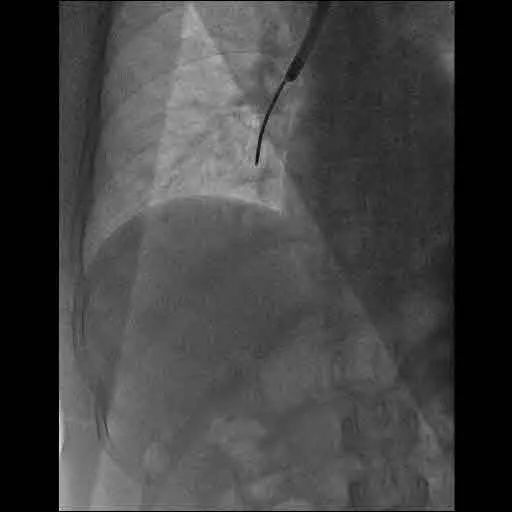

活检钳显影

完善术前准备后,结合胸部ct的大致定位,呼吸内科副主任医师在复杂的各级叶、段及亚段支气管中,顺利将支气管镜进入张奶奶的右中叶支气管,准确找到病灶位置。此时,在支气管镜下可以清晰地见到右中叶支气管粘膜充血水肿,内侧段上支有白色分泌物堵塞,在吸净后能看到右中叶内侧段粘膜糜烂,局部碳末沉积,触之易出血。在x线透视下,副主任医师精准地对右中叶内侧段上支处的病灶与内侧段上支开口处进行了活检、刷检及灌洗。术中患者未见并发症,术后安返病房。